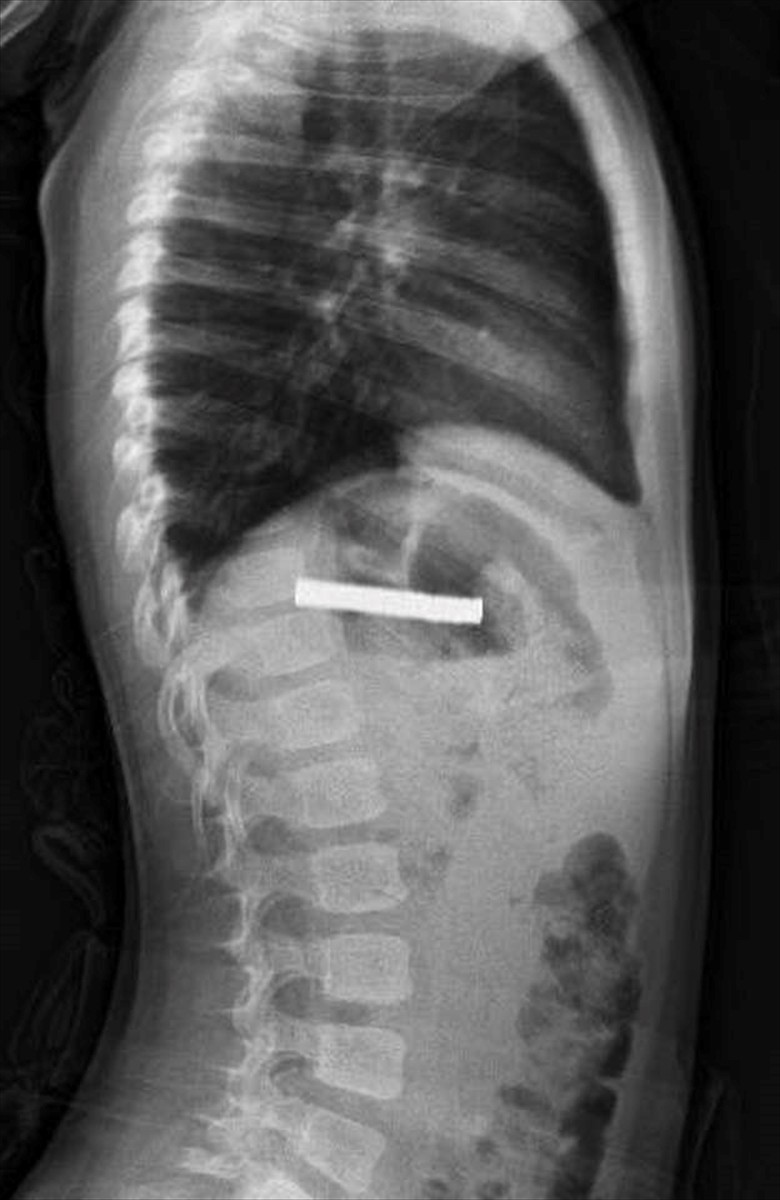

Elazığ'da 3 yaşındaki bir çocuk, oyun oynadığı sırada bulduğu 19 mıknatısı yuttuktan sonra rahatsızlanarak hastaneye kaldırıldı. Bu durum, Fırat Üniversitesi Hastanesi'nde gerçekleştirilen başarılı bir operasyonla son buldu.

Fırat Üniversitesi Çocuk Gastroenteroloji Hepatoloji ve Beslenme Bilim Dalı Başkanı Prof. Dr. Yaşar Doğan, burada yaptığı muayenelerde mıknatısların çocuğun yemek borusunu tıktığını belirledi. Doğan ve ekibi, çocuğun yemek borusundaki mıknatısları çıkarırken, işlem sırasında bazı hasarların oluştuğunu ancak iyi bir müdahale ile durumun kontrol altına alındığını ifade etti. "Mıknatıslar, hastanın midesine alındı ve oradan özel bir file ile çıkarıldı. İşlemden sonra çocuğu gözlem altında tuttuk ve sabah aile kendi isteğiyle taburcu olmak istedi," dedi.

Elazığ'da 3 yaşındaki çocuğun yuttuğu ve yemek borusunu tıkayan 19 mıknatıs, Fırat Üniversitesi Hastanesi'nde yapılan başarılı bir operasyonla çıkarıldı.